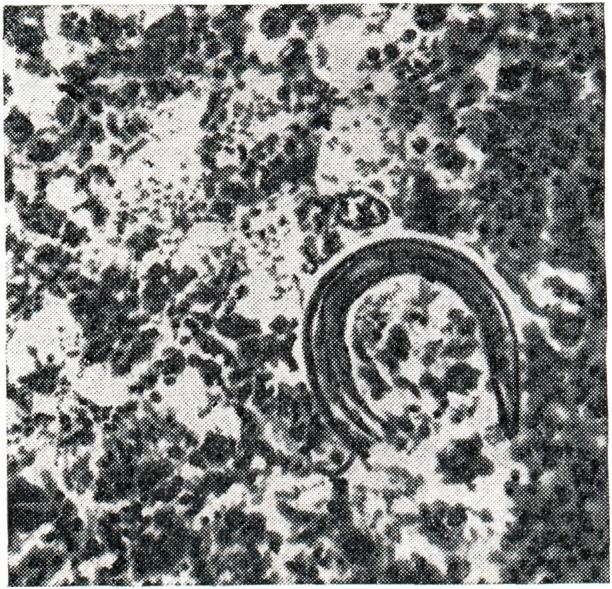

Аскаридоз имеет широкое распространение в зонах тропического, субтропического и умеренного климата (рис.4) при наличии достаточной влажности. Он отсутствует в зоне вечной мерзлоты и пустынях; редко встречается в сухих степях. Возможно, однако, образование микроочагов аскаридоза в местности, в целом не-благоприятной для их существования. Пораженность аскаридозом детей выше, чем взрослых, в результате недостаточного соблюдения ими мерличной гигиены и, возможно, вследствие развития у взрослых относительного иммунитета к аскаридозу в результате повторных заражений. Аскаридоз относится к геогельминтозам. Единственным источником инвазии является больной аскаридозом человек, в кишечнике которого паразитируют самцы и самки аскарид. Самка в сутки откладывает свыше 200 000 оплодотворенных незрелых яиц, которые с калом больного выделяются наружу. Созревание яиц происходит, как правило, в почве, при температуре от 10—12° (нижний порог) до 36° (верхний порог) и относительной влажности почвы не менее 8%.